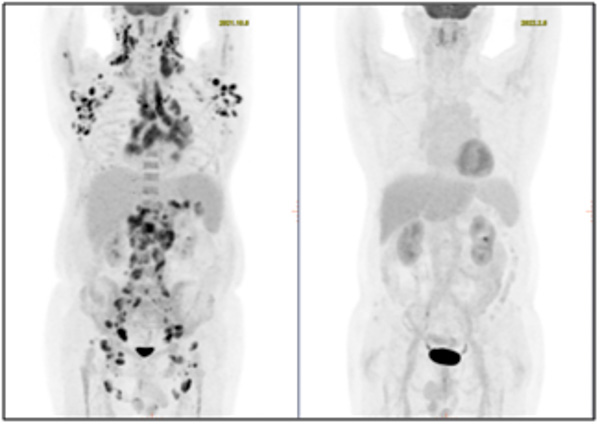

29歲潘先生,因“咳嗽咳痰、發(fā)現(xiàn)縱隔占位3天”到柳州市人民醫(yī)院就診,入院查胸部CT平掃提示:1.前上縱隔占位伴縱隔、兩側(cè)頸部淋巴結(jié)腫大,考慮惡性腫瘤伴淋巴結(jié)轉(zhuǎn)移瘤,擬伴上腔靜脈、升主動脈及右側(cè)胸膜、心包受累。2.右肺上葉受壓并阻塞性肺炎。3.心包及右側(cè)胸腔少量積液。后行縱隔腫瘤穿刺活檢術(shù),術(shù)后病理提示:彌漫大B細(xì)胞淋巴瘤。

為確定治療方案,了解其他部位是否有淋巴瘤浸潤,進(jìn)行了PET-CT檢查,患者全身MIP圖一目了然!縱隔巨大腫塊淋巴瘤,左側(cè)鎖骨上窩淋巴結(jié)淋巴瘤浸潤。

治療4周期后,患者癥狀好轉(zhuǎn),再次到核醫(yī)學(xué)科行PET/CT顯像檢查,如圖所示。

治療后前上縱隔軟組織較前明顯縮小,仍有腫瘤活性組織存在;雙側(cè)鎖骨上窩、縱隔2組淋巴結(jié)均已吸收、滅活;右側(cè)胸膜及心包稍增厚。治療后病灶較前明顯縮小、減少,極大地緩解了患者相關(guān)臨床癥狀。